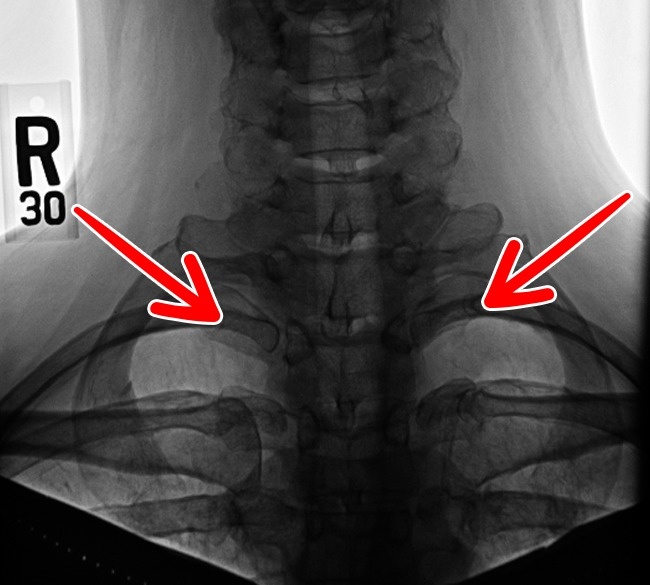

10. 第13对肋骨。

人类的近亲—大猩猩和黑猩猩就有多一对肋骨,但人类通常只有12对,只有8%的成人会多一对肋骨。